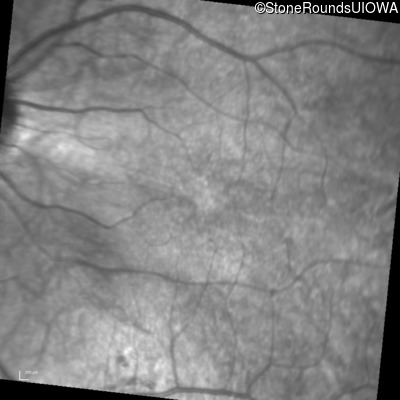

Infrared Fundus Photograph - Right - 20/50 -1

Exemplar